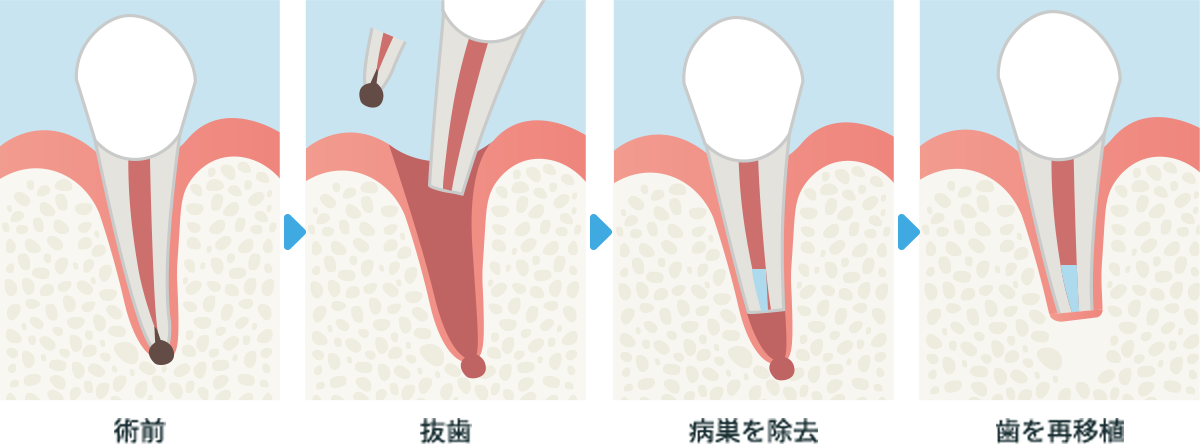

意図的再植術

歯茎をめくり確認することが出来ない位置であるなど、歯根端切除術では治療が困難な場合に、一度歯を抜いて歯の根の部分にあった病巣を掻き出し消毒してから歯を戻す治療です。

横スクロールで確認いただけます。